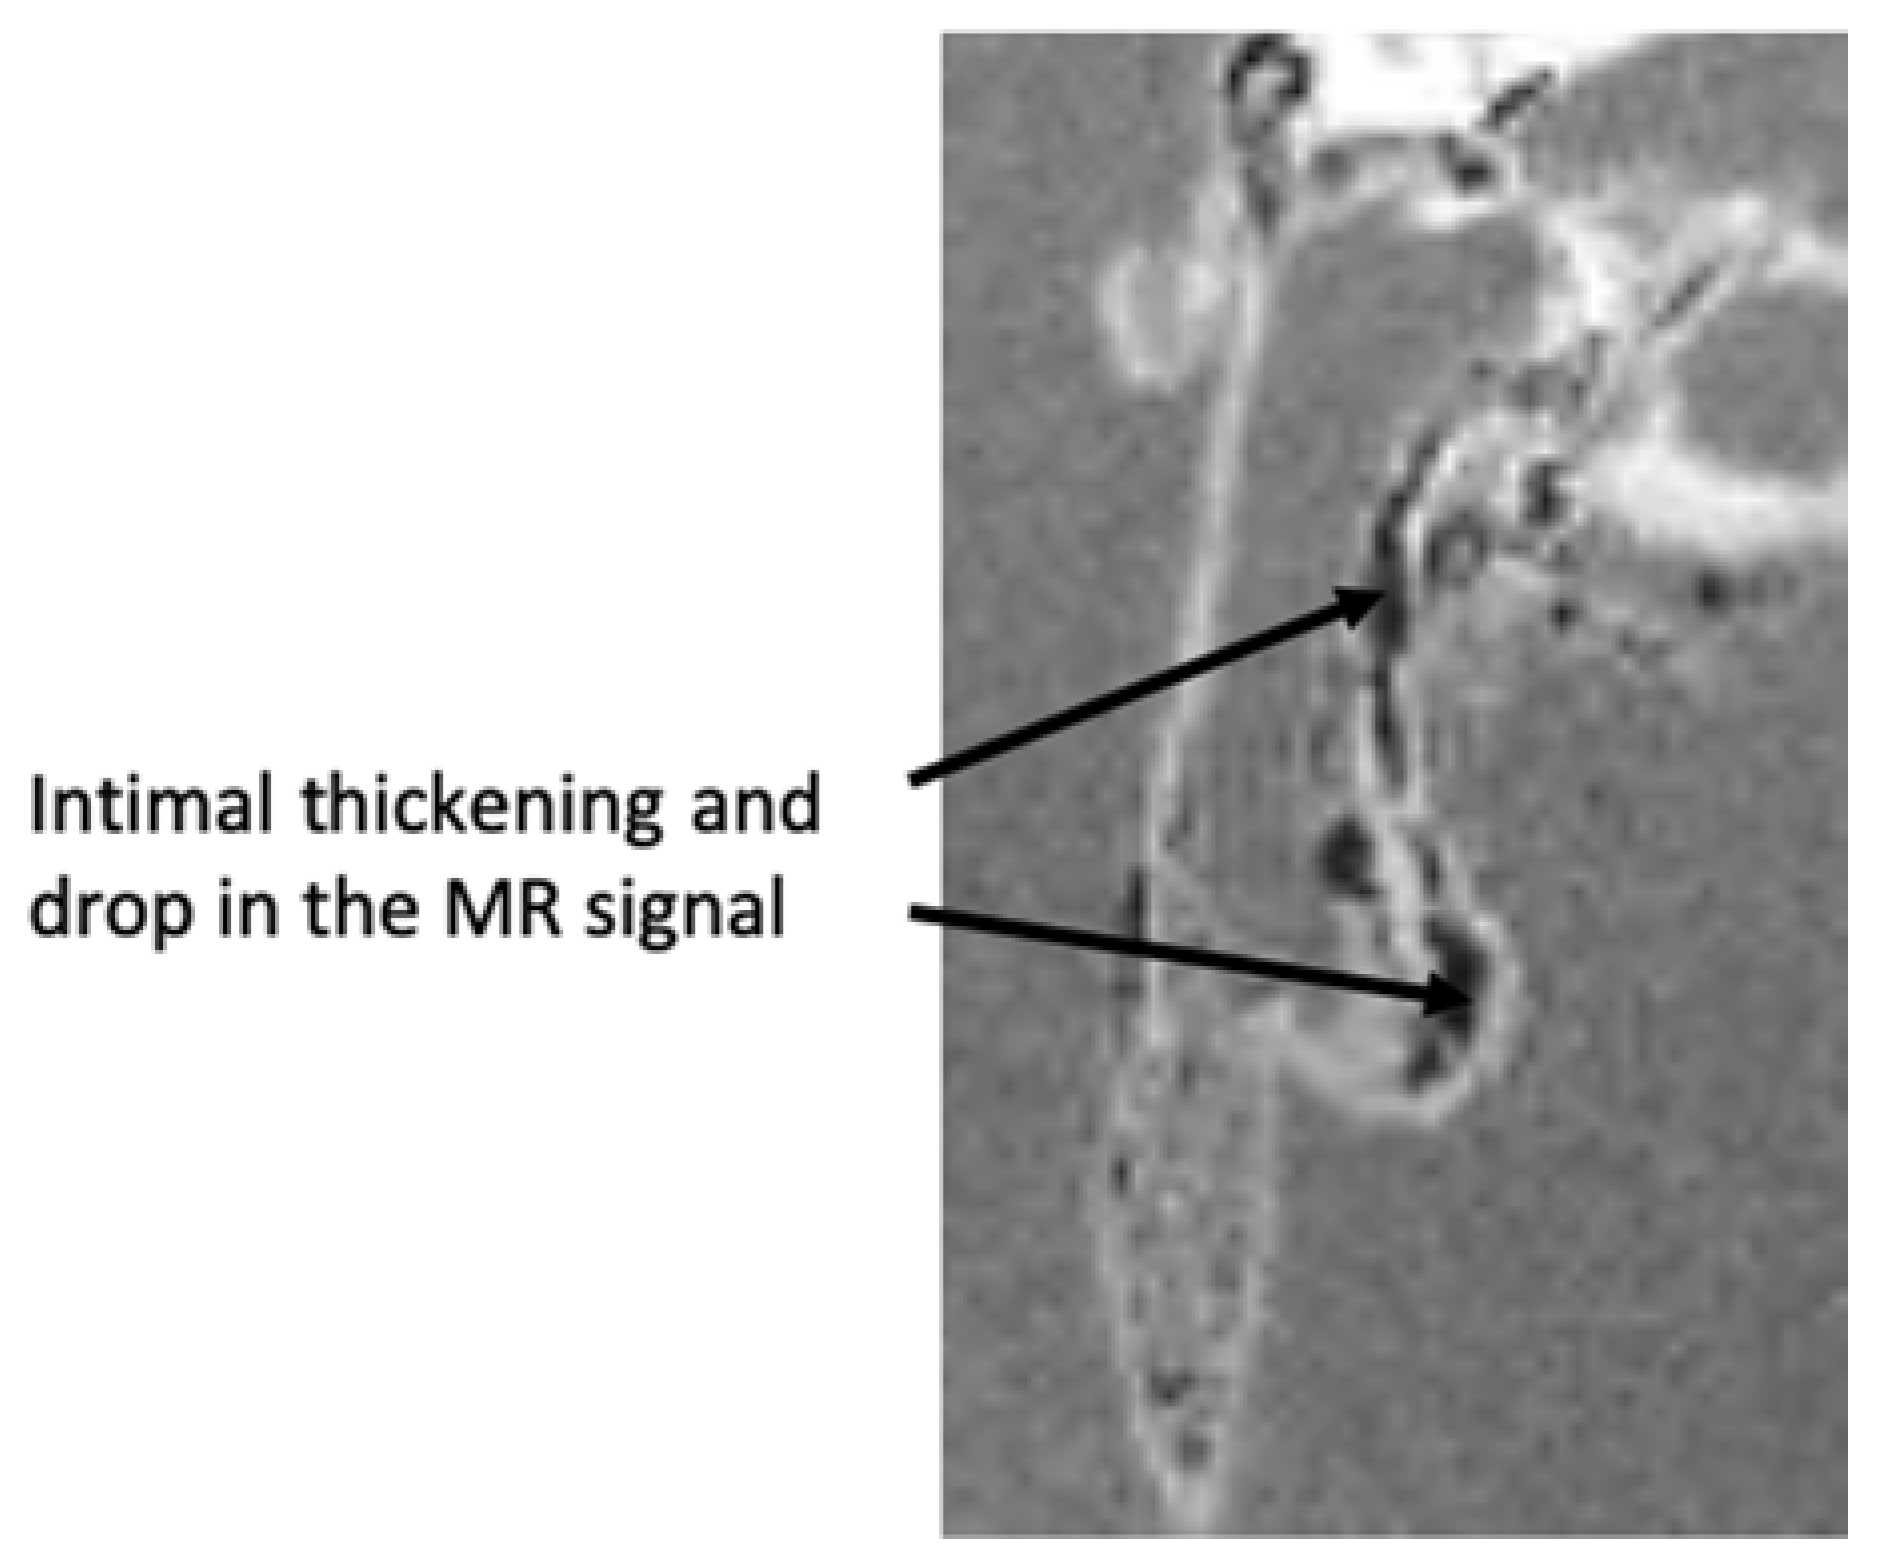

2.6.1. Ex Vivo MRI

4.8.1. MRI Analyses